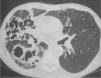

Se interpretó el cuadro como neumonía, posiblemente en relación con broncoaspiración inadvertida, y se trató con amoxicilina-ácido clavulánico (2g/8h, vía intravenosa). La evolución clínica fue favorable, pues mejoraron tanto el estado general como los síntomas respiratorios, la insuficiencia respiratoria y la alteración de las pruebas hepáticas. En la radiografía se observó una ligera mejoría. Se dio de alta al paciente con tratamiento antibiótico. Cuando acudió a revisión un mes después, presentaba un claro deterioro general, con pérdida de 4kg de peso, y refería expectoración abundante, purulenta y hemoptoica, pero no fiebre. En la radiografía de tórax se apreciaba un empeoramiento notable, con aparición de varias cavitaciones en el pulmón derecho y pérdida de volumen de éste (fig. 1). La TC torácica evidenciaba un patrón alveolar con cavitaciones que afectaban a los 3 lóbulos del pulmón derecho y a la língula (fig. 2). La serología para el virus de la inmunodeficiencia humana fue negativa en 2 determinaciones. Las baciloscopias y la técnica de reacción en cadena de la polimerasa para Mycobacterium tuberculosis en esputo fueron repetidamente negativas, así como los cultivos de micobacterias. La serología por inmunodifusión de inmunoglobulina G para H. capsulatum, Coccidioides immitis, Blastomyces dermatitidis y Paracoccidioides brasiliensis fue negativa. La broncoscopia no mostró alteraciones endobronquiales. Se tomaron muestras mediante catéter telescopado, lavado broncoalveolar y broncoaspirado, con resultados negativos para bacterias aerobias y anaerobias, así como para micobacterias. Finalmente en todas las muestras de broncoscopia, así como en la de punción transtorácica (realizada tras los resultados inicialmente negativos de la broncoscopia), se observó el crecimiento de un hongo dimórfico identificado unas semanas después, en el Centro Nacional de Microbiología de Majadahonda, como H. capsulatum.